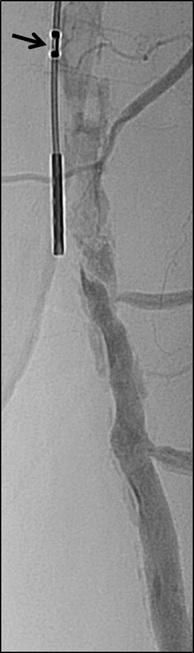

Crossing chronic total occlusion lesions are challenging procedures. The BeBack crossing catheter—Bentley’s first product to be available in both Europe and the USA following the company’s acquisition of Upstream Peripheral Medical Technologies’ GoBack crossing catheter in September 2022— offers a new solution in this space. In a Bentleysponsored advertorial, Andrej Schmidt (Leipzig, Germany) shares his clinical experience with the BeBack, noting how it has been a “gamechanger” in his endovascular peripheral arterial disease practice.

For more on this story go to page 19.